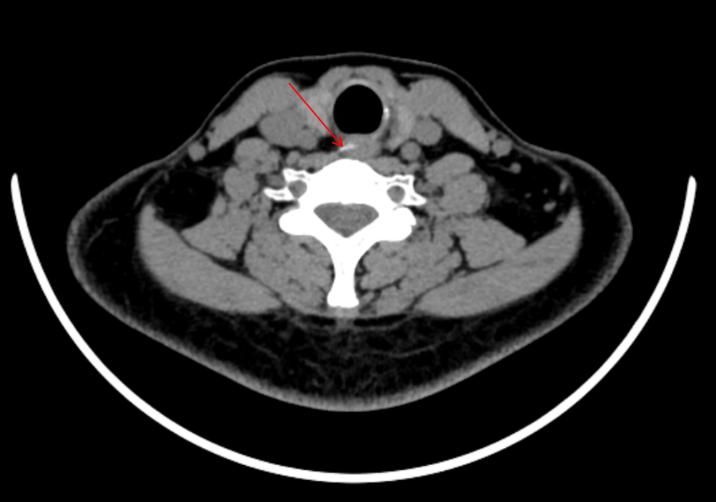

当日下午,41岁的常女士(化名)也因误食鸡骨头前来就诊。来院前两小时,她被鸡骨头卡住喉咙,随后出现咽部疼痛、呼吸困难、声音嘶哑等症状,情况十分危急。急诊CT检查提示,鸡骨头嵌顿于食管入口处。时间就是生命,我院消化内科陈芬荣副主任医师与助手安苗迅速组成救治小组,为常女士实施急诊异物取出术。医生们精准操作,成功将鸡骨头取出。患者的不适症状随即缓解,生命体征恢复平稳。